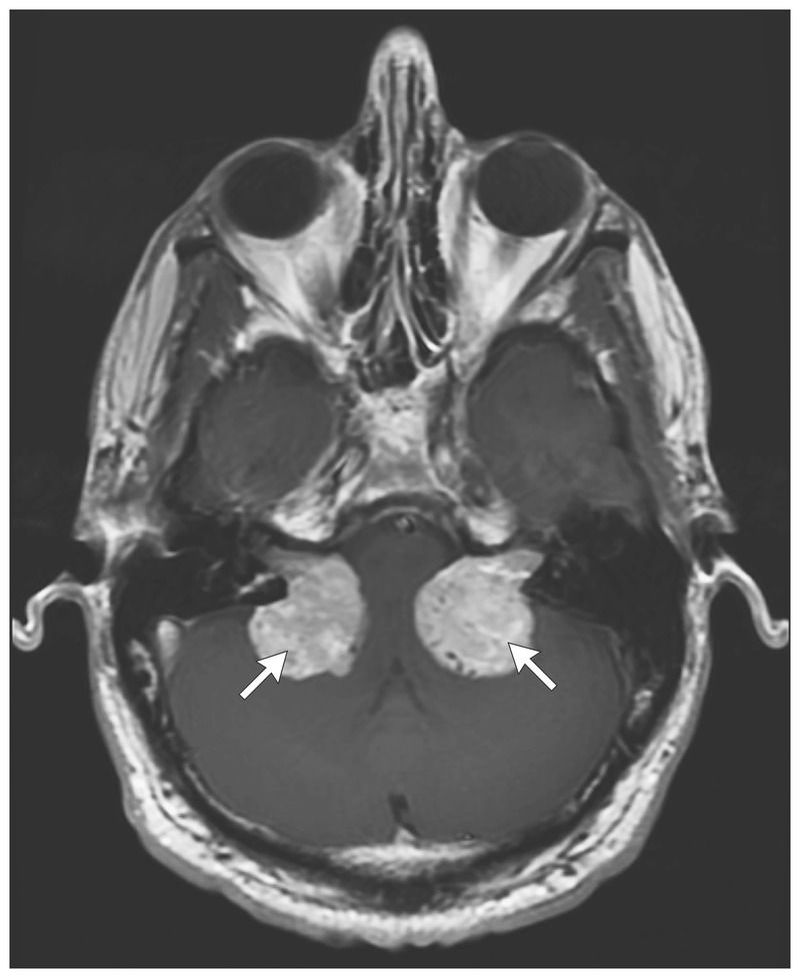

A 32-year-old man presented to the neurosurgery clinic with mild balance difficulties and hearing loss in the left ear. He had a family history of neurofibromatosis type 2 and a diagnosis of tumors in the right and left internal acoustic canals. He had not previously had symptoms related to the tumors (e.g., hearing loss or imbalance) and had been undergoing surveillance imaging of the brain since he was 16 years of age. Evaluation of the patient’s hearing revealed profound sensorineural loss on the left side and normal hearing on the right side. Magnetic resonance imaging of the brain performed after the administration of contrast material revealed tumors in both internal acoustic canals (33 by 26 by 31 mm on the left side and 32 by 28 by 30 mm on the right side), with extension in the cerebellopontine angles, and severe brain-stem compression. Bilateral vestibular schwannomas are a hallmark of neurofibromatosis type 2. In affected persons, there may be development of schwannomas on other cranial and peripheral nerves, meningiomas, ependymomas, and astrocytomas. Patients may have a parent affected with neurofibromatosis type 2, which is caused by mutations in NF2. These abnormalities are inherited in an autosomal-dominant manner, although de novo mutations may also occur. In this patient, left subtotal resection and stereotactic radiosurgical treatment of the left tumor were performed. Within 5 years and 11 months after initial presentation, the profound hearing loss in the left ear persisted, but the difficulties with balance had resolved. The patient continues to have annual hearing tests and MRI of the brain and has had no new symptoms at follow-up.